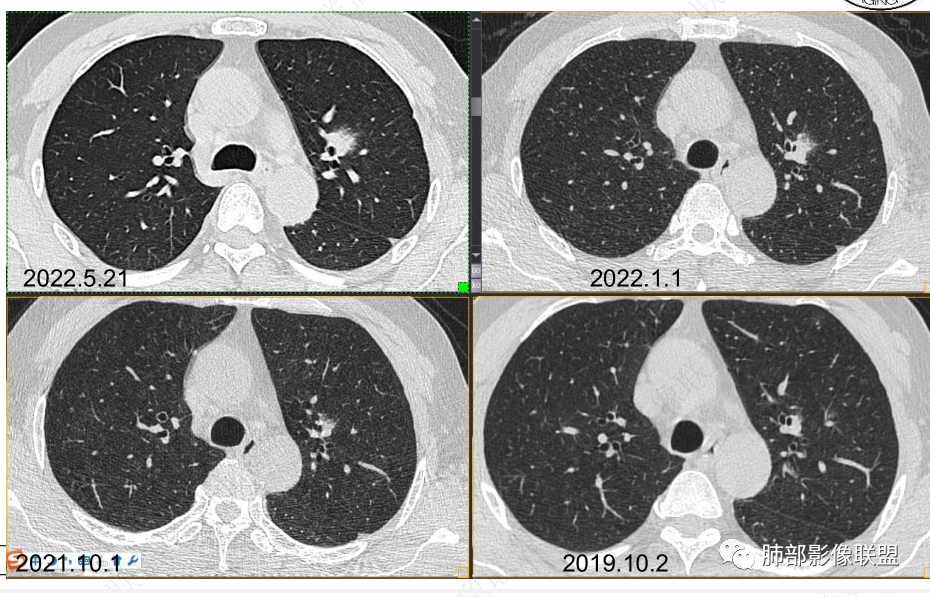

男性,肺结节3年,发现逐渐增大,影像表现,左肺舌段结节,边缘可见磨玻璃密度影,内部走形下舌段支气管变窄,增强呈持续强化,首先考虑肺腺癌,鉴别炎性肉芽肿,真菌/隐球菌。

中老年男性,发现结节,影像表现,左肺上叶结节,实性部分有膨胀性生长,边缘可见磨玻璃影,似清晰似不清晰,病灶与支气管关系密切,部分支气管似狭窄及僵硬,增强病灶强化明显,考虑腺癌(粘液性腺癌)鉴别炎性肉芽肿。

中老年男性,左肺上叶中轴区实性结节及周围磨玻璃影,磨玻璃边界似清非清,关键点2019.10-2021.10-2022.05结节持续增大,增强后明显强化。考虑恶性结节可能大,腺癌(黏液腺癌)?鉴别炎性结节。

57岁,属于高危人士;病灶3年逐步增大,肿瘤按理是要考虑的

初始病灶应该是这里

病灶朝前、外侧进展

病灶包括两部分

1、实性2、周围GGO